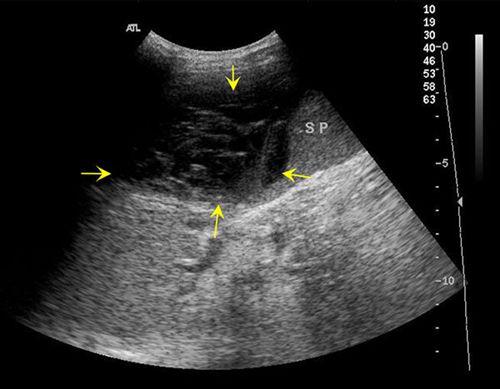

通常情况下,可以用彩色多普勒超声诊断仪来诊断是否发生脾破裂或鉴定脾脏受损程度。这是一种非侵入性检查,较常用,能显示破碎的脾脏,较大的脾包膜下血肿及腹腔内积血。

脾破裂可分为以下三种类型:

①真性脾破裂,破损累及包膜,引起不同程度的出血,即脾周围血肿或游离性腹腔内出血,后者易于导致失血性休克;

②中央型破裂,即破裂发生在脾实质内,引起实质挫伤、实质内多发性小血肿或较大血肿;

③包膜下破裂,引起包膜下血肿。